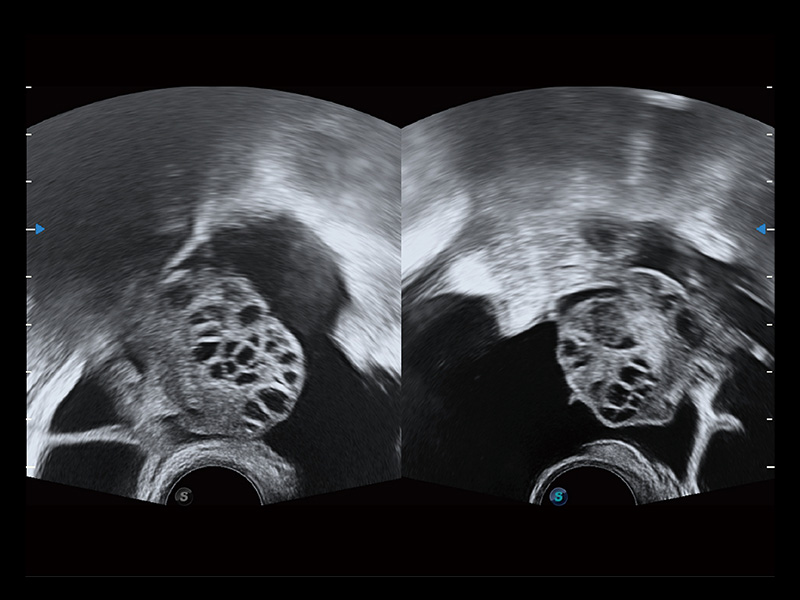

“生育问题”即关系民族复兴,也关系亿万家庭的幸福。随着婚育年龄推迟、社会压力增加等因素,越来越多人群也面临着“生不出、生不好”的问题。辅助生殖作为治疗不孕不育最有效的方法之一,也逐渐成为育儿新希望。而超声检查能为生殖需求人群的初诊评估提供宝贵的信息。 P20 Elite是玖鼎集团匠心打造的一款生殖应用型彩超。她继承玖鼎集团高端极光平台,突破性地将多款新型芯片及硬件模块进行整合,均衡了高端系统性能与小巧灵动机身。P20 Elite卓越的图像质量搭载专科探头,旨在为您提供全面的辅助生殖解决方案。

P20 Elite配备了丰富的生殖探头群和临床应用功能,在卵泡监测、穿刺取卵、胚胎移植、妊娠确认等领域,为生殖需求人群提供了新的临床机会,重新定义高端超声如何应用于生殖健康检查。

通过线上云会诊平台,实现县级医院与上级医院患者卵泡数据互联互通。避免重复性卵泡测量,提高诊断效率。